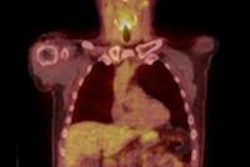

Researchers at the Greater Poland Medical Centre in Poznan conducted a retrospective study of patients treated for head and neck squamous cell carcinoma to compare the diagnostic performance of PET/CT and ultrasound, as well as their combined use to detect local recurrence. Their objective was to determine the effectiveness of the examinations with respect to identifying cancer in patients whose clinical otolaryngological exams did not reveal any sign of cancer recurrence.

A total of 36 patients developed a recurrence at a mean follow-up of 10 months, none of whom exhibited any clinical indications of cancer. PET/CT had sensitivity of 86% and specificity 82%, and ultrasound had sensitivity of 81% and specificity of 87%.

The positive predictive value was 83% for ultrasound and 79% for PET/CT. Negative predictive value was slightly higher for PET/CT at 89% compared with 85% for ultrasound.

Lead author Dr. Malgorzata Wierzbicka, of the department of otolaryngology of Poznan University of Medical Sciences, and colleagues relied on lymph node size and shape criteria to determine abnormalities, whereas PET/CT provided additional information about metabolism and precise localization of the occult recurrence.